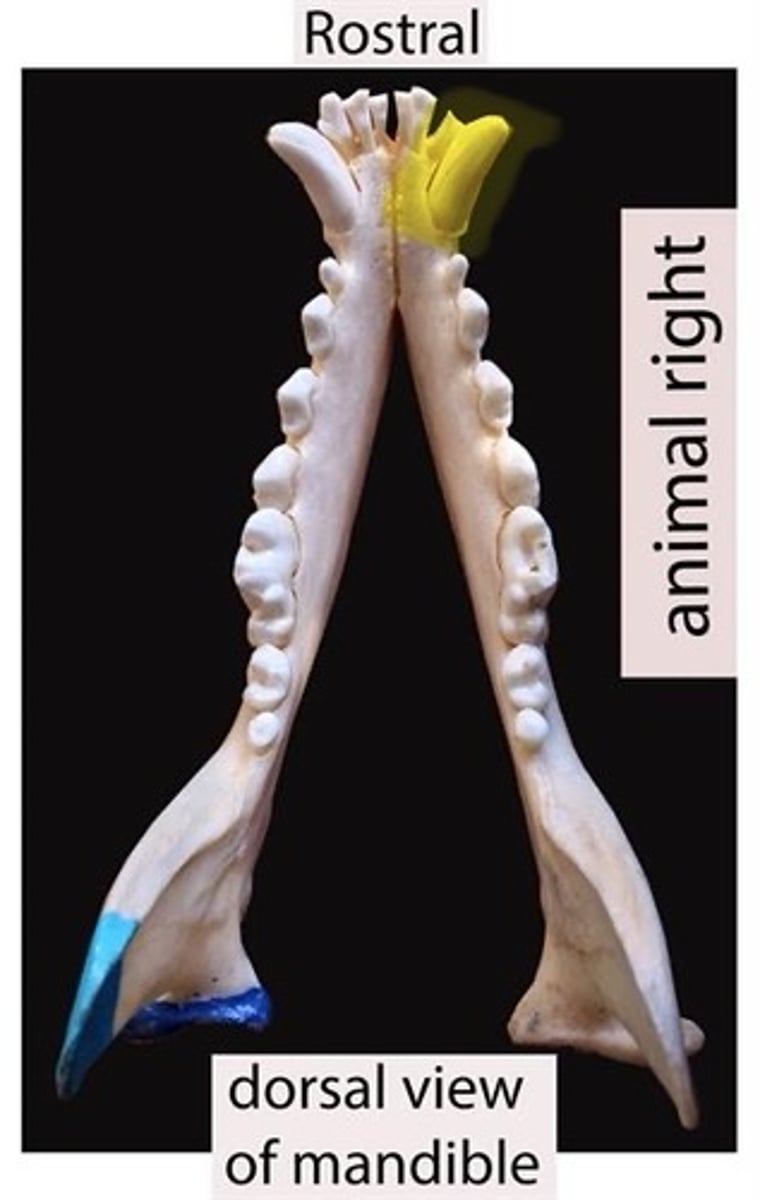

Identify the type of teeth shaded.

premolars

Identify the type of teeth shaded.

Canines

Identify the type of teeth shaded.

Molars

Identify the type of teeth shaded

Premolar

Identify the type of tooth indicated by the arrow.

Molar

Identify the type of tooth indicated by the arrow.